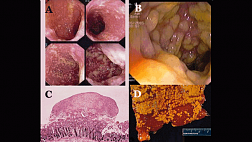

Аутоиммунный гастрит. НЭО желудка.

Куваев Роман Олегович

Эндоскопическая диагностика и лечение нейроэндокринных опухолей ЖКТ

Малихова Ольга Александровна